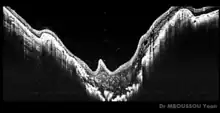

Morning glory syndrom OCT

Morning glory syndrome optical coherence tomography (OCT)